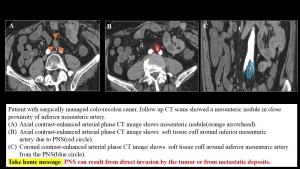

Rectal cancer

In rectal cancer, perineural spread carries a poorer prognosis .Tumor may track along the lumbosacral plexus, sciatic, obturator, and spinal nerves, frequently starting with the inferior hypogastric plexus. On imaging, PNS appears as nodular thickening and enhancement of the perirectal fascia extending toward the lumbosacral plexus. This plexopathy may result from direct tumor infiltration or metastatic deposits.